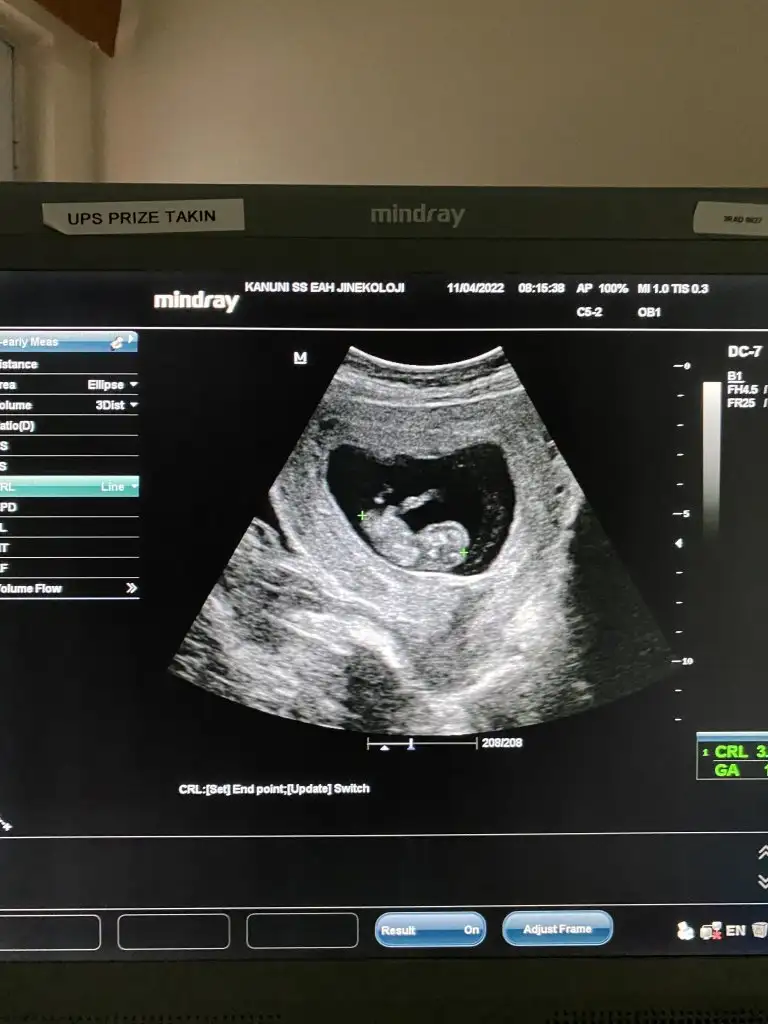

11+5 canım yüzde 90 erkek dedi bacak arasında bi sey gördük gibi sen ne diyorsun:)

• IMG-20220429-WA0022.webp

IMG-20220429-WA0022.webp

33,9 KB · Görüntüleme: 81

• IMG-20220429-WA0020.webp

IMG-20220429-WA0020.webp

37,9 KB · Görüntüleme: 88